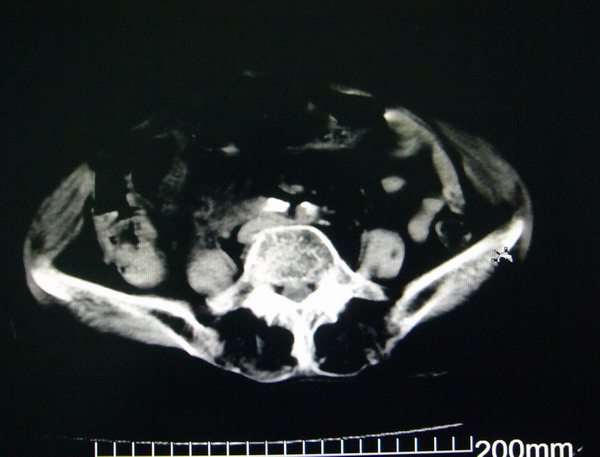

女:83y,转移性右下腹痛2小时,白细胞计数增高。

1.右侧肾盂扩大,肾盏无扩张,考虑:先天性肾盂变异可能性大。

2.胆囊扩张,考虑:胆囊炎。

3.阑尾区域可见以结节样高密度影,结合病史,考虑:阑尾结石,阑尾炎。

右下腹肠系膜增厚,结合病史支持阑尾炎.

右侧壶腹型肾盂可能,建议输路造影或增强

1.右侧肾盂扩大,考虑先天性肾盂变异或肾盂旁囊肿。

2.胆囊扩张,考虑胆囊炎。

3.阑尾区域可见结节样高密度影,结合病史考虑:阑尾结石、阑尾炎。